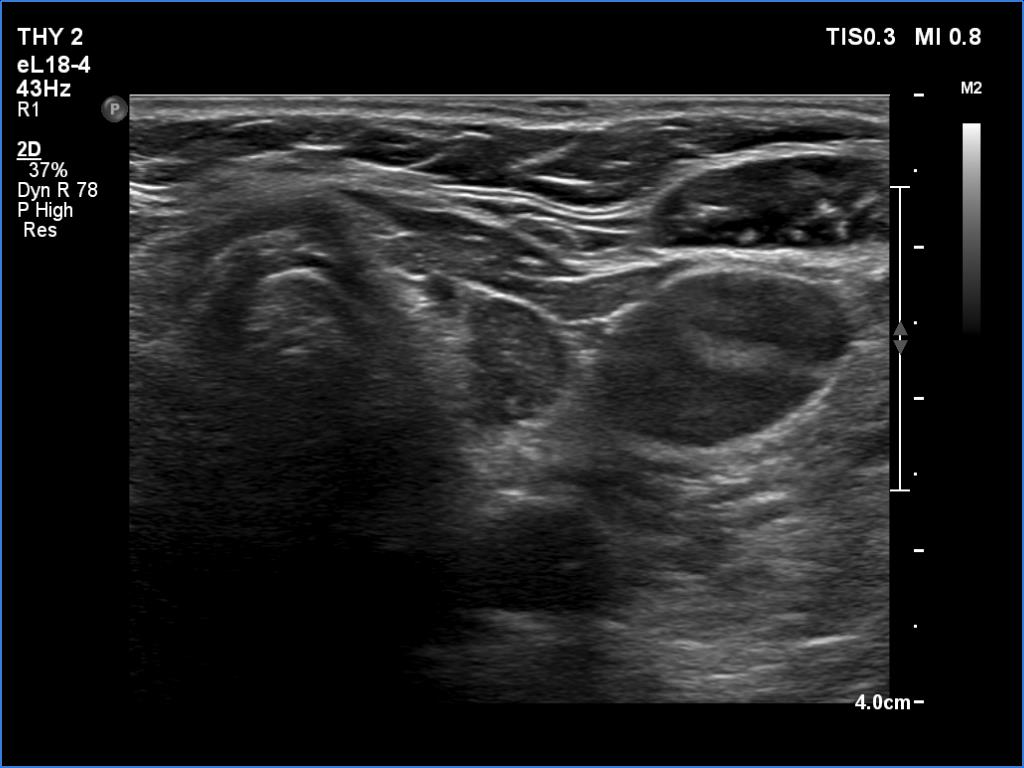

Ultrasonography: The right lobe had several discrete hypoechoic areas within an echonormal background. The left lobe had a larger hypoechoic area resembling the presentation of central hypoechoic area-type form.

Comment: The central hypoechoic area-type presentation is always bilateral. The pattern in this case should be regarded as focal form of lymphocytic thyroiditis.